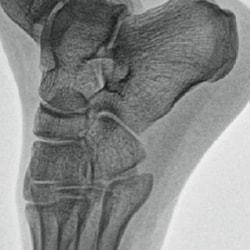

Metal correction

Minimizing halation for clear visualization in orthopedic procedures with bolts and implants.

No metal correction